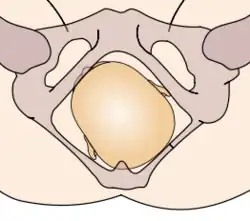

Durante la mecánica del parto, los diámetros menores del feto pasan por los diámetros mayores de la pelvis materna. Con el fin de no quedar encajado en algún punto durante su trayectoria fuera del útero, el neonato pasa por una serie de movimientos naturales que constituyen el mecanismo del parto.

- Descenso: ocurre por acción de la gravedad una vez dilatado el cuello uterino, así como de las poderosas contracciones uterinas y de los músculos abdominales maternos. El descenso tiende a ser lentamente progresivo basado en la estructura pélvica materna.

- Flexión: la cabeza del feto se flexiona, de modo que el mentón fetal hace contacto con su pecho, al encontrarse el primer punto de resistencia del piso pélvico.

- Expulsión: el hombro púbico tiende a salir primero, seguido por el hombro perineal. El resto del cuerpo sale por sí solo con una leve impulsión materna.

Estos movimientos son todos debido a la relación que existe entre la cabeza ósea y hombros del feto y el anillo óseo de la pelvis materna.